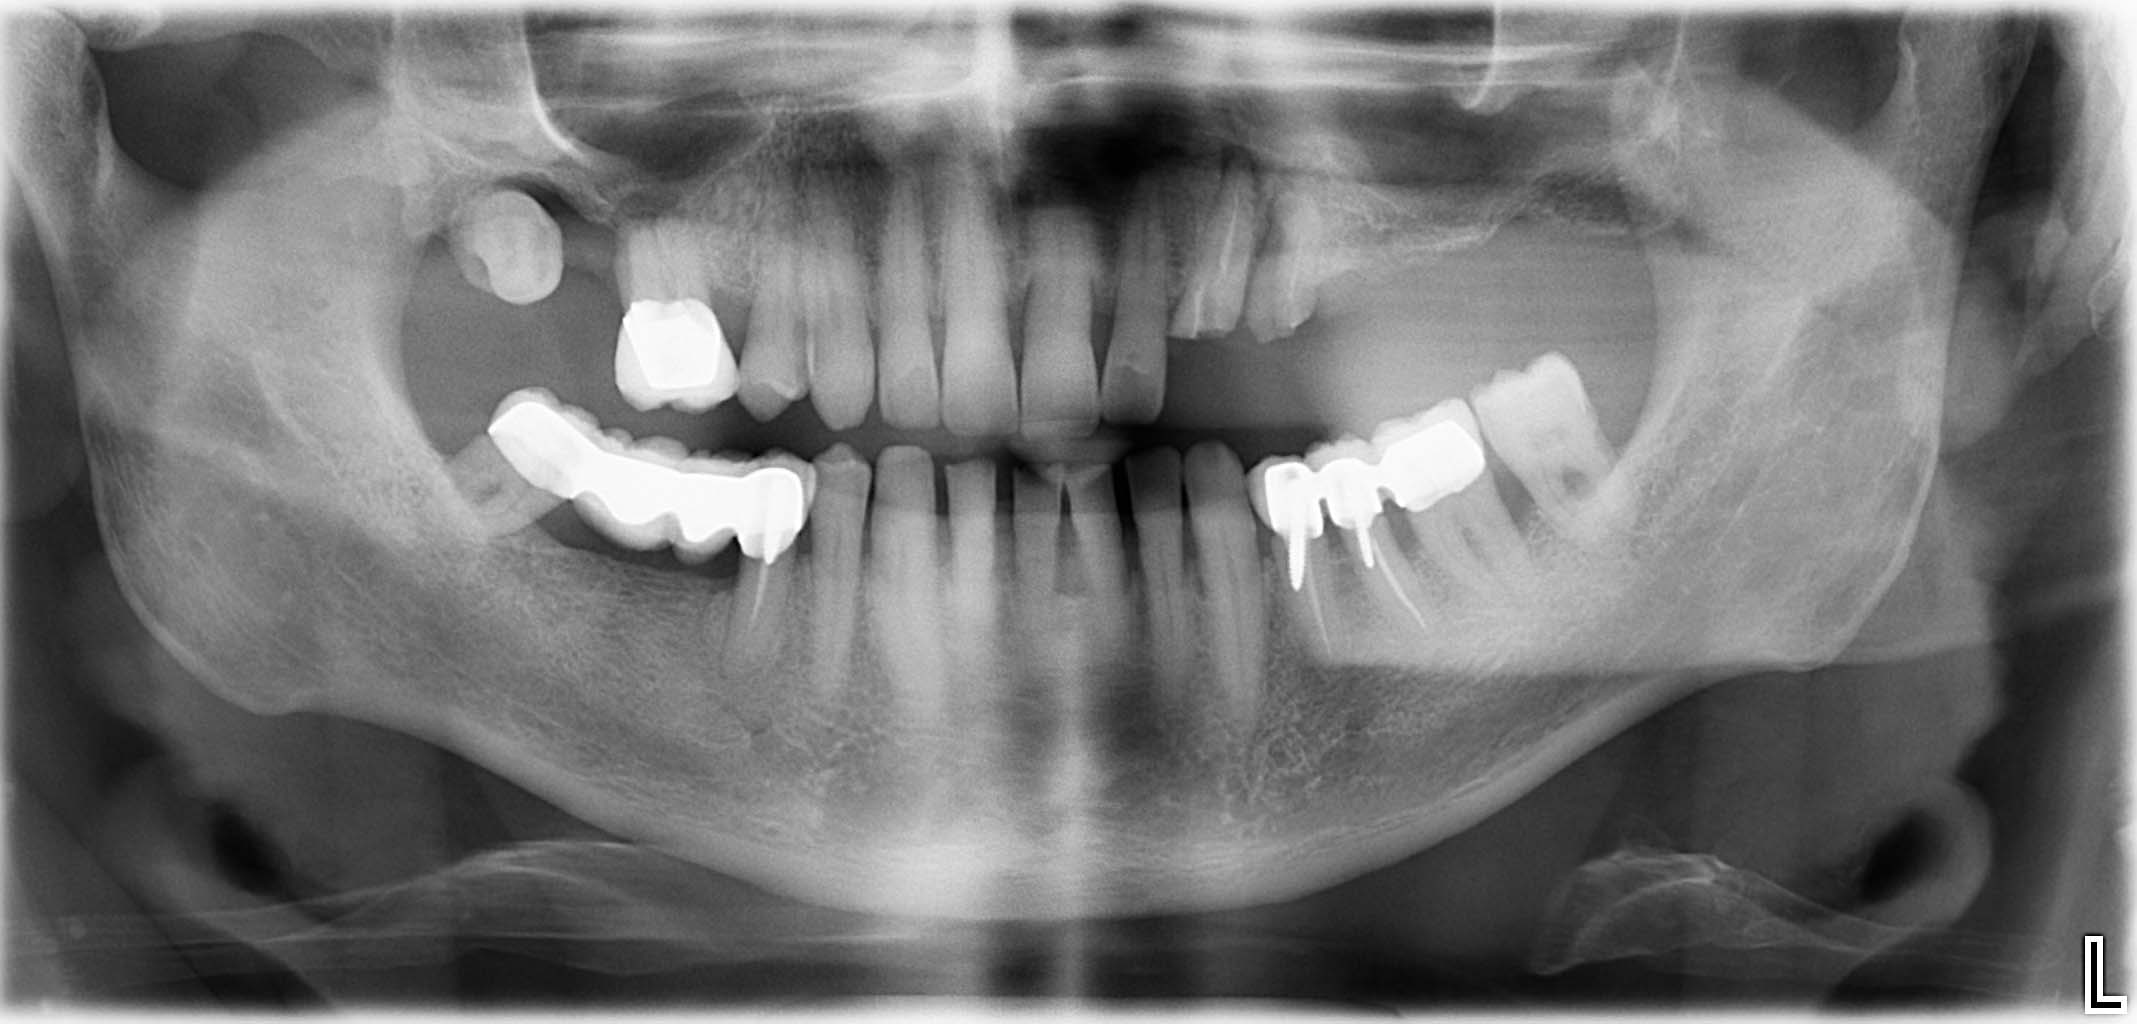

Erfolgreich implantierte Patientenfälle (klinische Fotos)